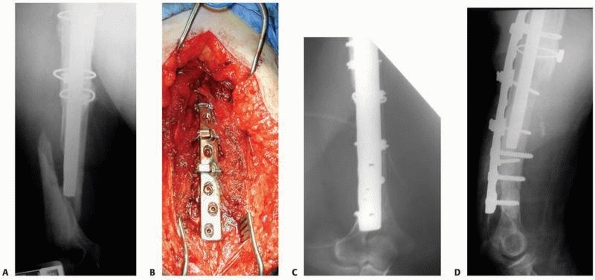

|

FIGURE 21-15 Treatment of a periprosthetic distal femur fracture (A,B) with a lateral locking plate (C,D).